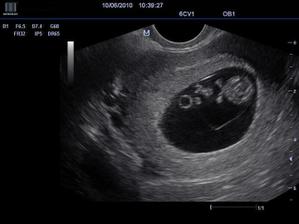

Naše bábätko

@miyya bolo to nádherné, videli sme ako sa hýbalo 🙂 drahý to rozdýchal až večer celý deň bol z toho mimo